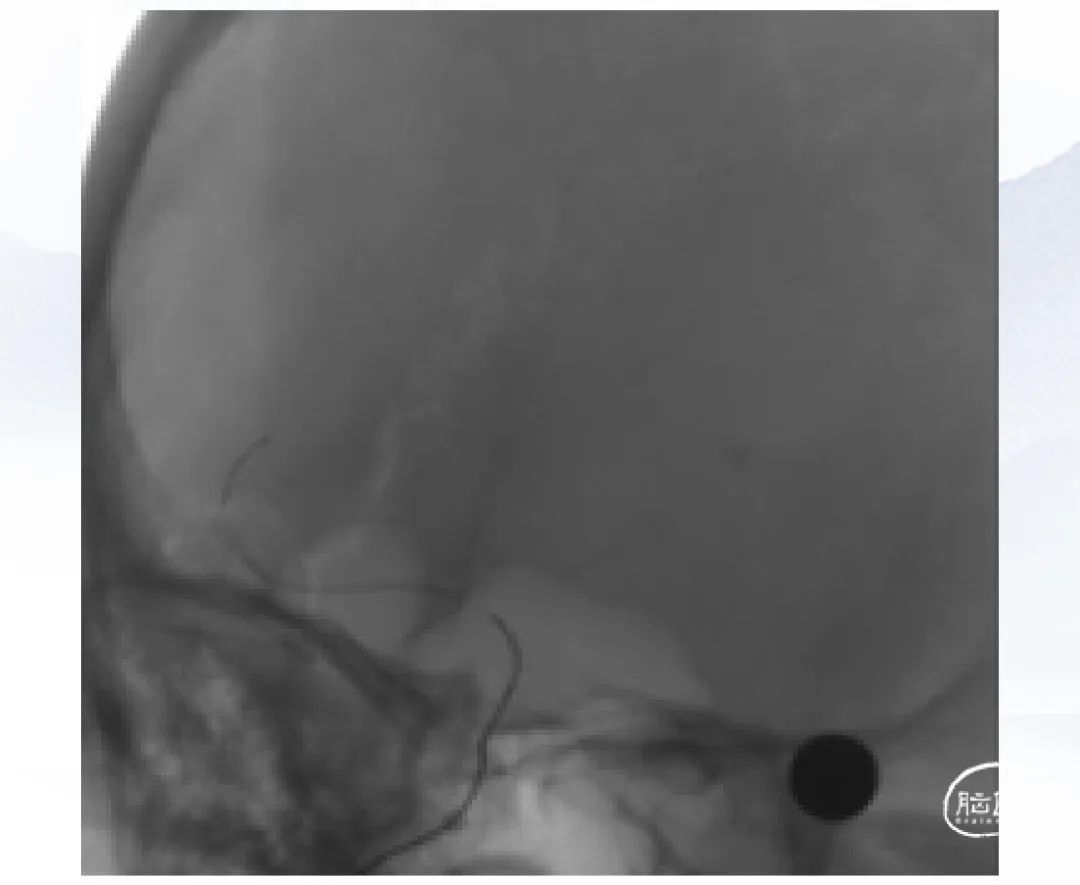

上海心玮医疗科技股份有限公司(股票代码:06609.HK)成立于 2016 年,公司致力于提高创新医疗技术的可及性,守护生命健康。六年时间,心玮医疗在神经介入领域开拓性地打造了国内首个卒中治疗及预防一站式解决方案,拥有从急性缺血性卒中和神经血管狭窄治疗、缺血性卒中预防、出血性卒中治疗到介入通路器械的全产品管线,申请专利超过 100 项,产品年产能超过 15 万件,销售渠道覆盖国内超过 30 个省(含直辖市和自治区)的 1400 多家医院。